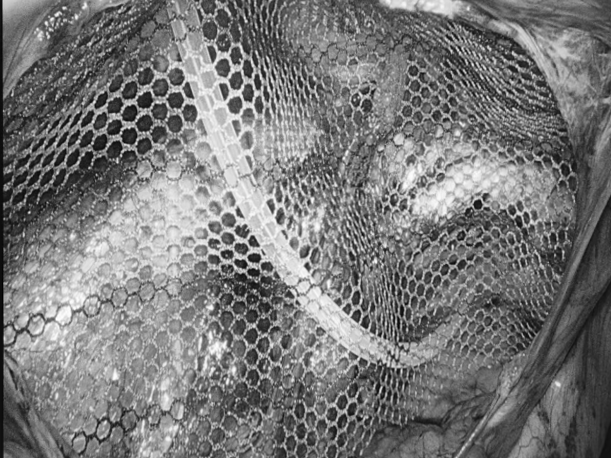

一名女性患者长期受到下腹部坠胀、排便不适等症状困扰,近期发现盆腔内存在肿物,严重影响其生活质量,为寻求进一步诊治,她前往贵州航天医院普外科就诊,经核磁共振(MRI)检查提示:盆腔内直肠与骶骨之间有一个“骶前囊肿”。由于该囊肿位置深,且与周围重要的神经和血管关系密切,若采用传统手术不仅创伤大,还伴随一定的风险。 面对这一棘手难题,普外科立即组织了麻醉科、医学影像科、妇科、重症医学科在内的多学科专家会诊(MDT)。经专家团队详细评估,与患者及家属充分沟通后,为患者制定并成功实施了“腹腔镜下骶前囊肿切除术”。术后恢复良好,不久便康复出院。 【疾病科普|什么是骶前囊肿?】 骶前囊肿,可以理解为生长在骨盆最深处、直肠后方的一个囊性肿物。由于它“躲藏”的位置非常特殊,四周紧邻着控制排便和感觉的重要神经与血管,因此被视为盆腔外科手术中的一个难点。 它可能带来哪些影响? 1.随着囊肿逐渐增大,可能会压迫直肠,引起排便困难或坠胀感。 2.压迫骶神经,可能导致腰骶部或会阴区的酸胀、疼痛。 3.囊肿本身也可能发生感染,形成脓肿,加重不适。 【技术介绍|腹腔镜下骶前囊肿切除术】 对于骶前囊肿这类较深的病灶,腹腔镜下骶前囊肿切除术提供了一种更为微创、便于操作的解决方案。 它是如何进行的? 医生仅通过腹部几个约0.5-1厘米的小孔,其中一个孔放入带高清摄像头的腹腔镜,将盆腔内的景象放大并清晰地投射到屏幕上,如同给了医生一双进入体内的“眼睛”。其他几个小孔则伸入细长的专用手术器械。医生看着屏幕,遥控这些器械,在清晰的视野下精细地分离并完整切除囊肿。 腹腔镜微创手术的特点包括: ▶创伤较小:避免了传统手术的长切口,体表疤痕小。 ▶视野清晰:放大后的图像让医生能更清楚地分辨囊肿与周围重要结构。 ▶操作精准:有助于更完整地切除囊肿,并尽力保护盆腔神经功能。 ▶恢复较快:因手术创伤小,患者术后疼痛感更轻,下床活动早,住院时间也可能缩短。 注:本文旨在进行健康科普,分享医疗案例与科普知识,不能替代任何专业的医疗建议。如有任何健康问题,请务必及时咨询并遵从专业医生的诊疗意见。 贵州航天医院普外科专家简介 高大勇 普外科(肛肠外科)学科带头人、名誉主任,主任医师、教授 临床擅长:对中西医结合诊治肛肠学科各种常见病、多发病及疑难杂症等具有丰富的临床经验。 原遵义市第一人民医院(遵义医科大学第三附属医院)、遵义市中医院肛肠科主任。中华中医药学会肛肠分会常委,全国中医肛肠学科名专家,中国健康促进与教育协会肛肠分会常委,中国康复医学会肛肠疾病康复专业委员会常委,中国民间中医医药研究开发协会肛肠分会副秘书长,中国医师协会中西医结合肛肠医师专业委员会常委,国家二级心理咨询师,贵州省第一批中医名医工作指导老师,遵义市名中医,遵义市肛肠学会会长,遵义市肛肠质控中心名誉主任,遵义市中西医结合学会名誉会长,遵义市健康科普专家,原贵州省中西医结合学会肛肠分会副主任委员、贵州省中医肛肠质控中心副主任、遵义市医学会医疗鉴定委员会专家、遵义市卫生系列高级评委。发表论文30余篇,主编和参编医学著作5本,主持省级科研课题2项、市级科研课题2项、院级科研课题1项。 梁 跃 普外科党支部书记、主任,主任医师 临床擅长:对普外科各类肿瘤手术具有丰富的临床经验。 毕业于遵义医学院,遵义市医学会小儿外科学分会常务委员,遵义市肛肠协会理事,遵义市医学会核医学分会(第二届)委员会委员;荣获第三期“黔医人才计划”优秀学员称号;主持市级课题1项,完成省级课题1项,在国内各类刊物上发表论文10余篇。 钱科洪 民盟盟员,普外科副主任医师 临床擅长:从事普外科临床工作30余年,对各类普外科疾病的诊治、乳腺、甲状腺、胃十二指肠、结直肠等疾病及疑难杂症具有丰富的临床经验。 毕业于遵义医学院临床医疗系,2009年前往中山大学附属第一医院微创外科进修学习,在国内各专业期刊发表论文数篇。 贵州航天医院普外科简介 基本情况 贵州航天医院普外科成立于1968年,前身属于原航天部O61基地3417医院外一科,1998年3417医院、3427医院合并后更名为普外科,下设胃肠外科、肛肠外科2个亚专业科室,拥有在全市较为先进的专科设备和技术,是中国疝病专科联盟单位,贵州医科大学附属医院胃肠外科专科联盟单位。开放床位40张,配备医护人员21人。 专科特色 普外科致力于胃肠及肛肠疾病的外科临床诊治及科研,以腹腔镜微创外科技术为本,形成以快速康复治疗胃肿瘤、结直肠肿瘤、小肠肿瘤、直肠脱垂、肥胖病、急腹症、各类疝、痔、瘘等专科特色,同时注重胃肠疾病尤其是结直肠恶性肿瘤的基础研究和临床转化研究,总体诊断和治疗水平在区域同级医院居于领先水平。 开展手术:腹腔镜下胃癌根治术,腹腔镜下袖状胃切除术,腹腔镜下胃肠道间质瘤切除术,腹腔镜下结、直肠癌根治术,胃癌、结直肠癌的精准治疗,腹腔镜下小儿疝气、成人疝修补术,腹腔镜下阑尾手术,内痔的硬化注射治疗及痔疮的微创治疗:ATH、PPH、TST,直肠脱垂的各种手术治疗,难治性伤口VSD技术,鼻胃肠管、肠梗阻导管置入术,肛肠术后间歇性导尿技术,并引进了中医适宜技术,也为各种化疗患者提供输液港安装,提高患者就医体验。 腹腔镜下腹股沟疝 无张力修补术 腹股沟疝里金斯坦 (Lichtenstein)手术 PPH微创术治疗环状混合痔 黏连性或炎性肠梗阻-肠梗阻导管 腹腔镜袖状胃切除 腹腔镜阑尾切除术 腹腔镜阑尾肿瘤切除术 腹腔镜下结肠癌根治术 诊疗范围 胃肿瘤、结直肠肿瘤、小肠肿瘤、肥胖症、各类急腹症、腹部外伤、腹壁疝、便秘、直肠脱垂、痔疮、肛瘘、肛裂等胃肠、肛肠外科疾病。 END